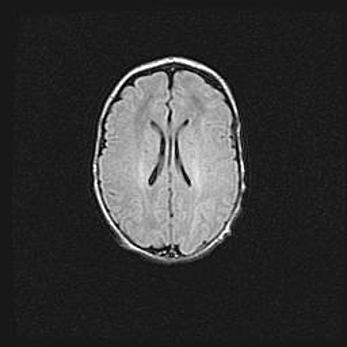

Открытая гидроцефалия.

Возраст: 9 месяцев 12 дней

Вес: 6800 г

Пол: мужской

Окружность головы: 41,5 см

Срок гестации: 28 недель

Гидроцефалия головного мозга у новорожденных имеет характерный признак: опережающий рост окружности головы приводит к визуально хорошо определяемой гидроцефальной форме сильно увеличенного в объёме черепа. Детские неврологи определяют следующие симптомы гидроцефалии у грудничков: выбухающий напряжённый родничок, частое запрокидывание головы, смещение глазных яблок к низу.